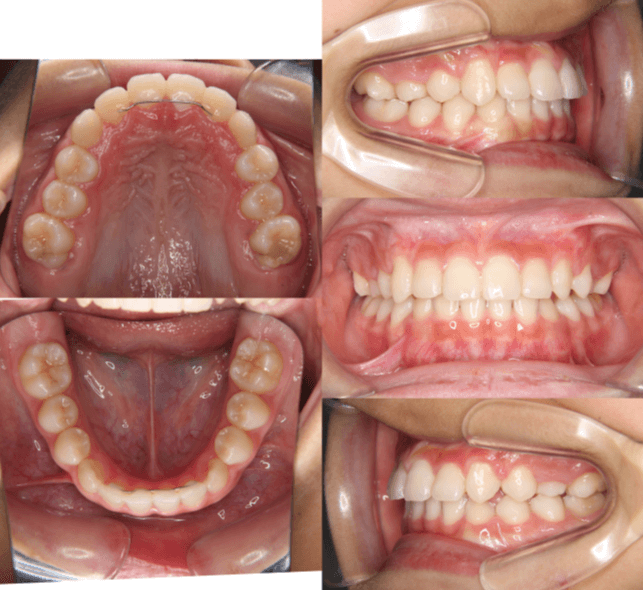

早期矯正治療 交叉咬合症例

主訴 | 前歯の咬み合わせが逆になっており、歯根や歯肉への影響を懸念されて来院された患者様です。 |

---|---|

診断結果 | 8歳9か月の男児。 上下前歯の交叉咬合と、下顎前歯部の歯肉退縮傾向が認められました。 |

治療内容 |

|

治療後の経過 |

治療期間 | 動的治療期間:3年7か月 通院回数:20回 |

治療費用 | 460,000円(税別) |